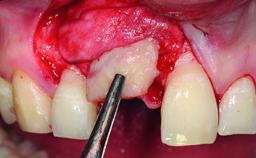

Replacement of an Ankylosed Upper Left Central Incisor: Bone Augmentation and Socket Grafting, Late Placement of an RC Bone Level Implant

| Bone Augmentation | Horizontal|Simultaneous|Staged |

| Augmentation Materials | Autogenous chips|Xenogenous |

| Bone Volume | Deficient horizontally, requiring prior grafting |